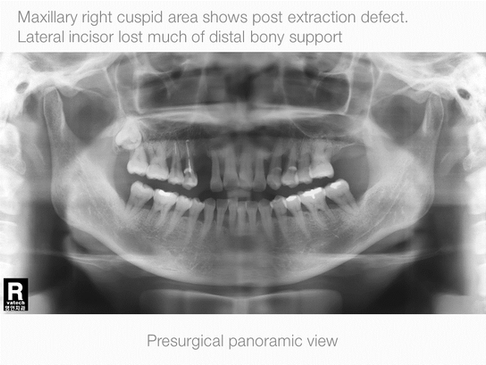

Vertical Augmentation

Maxillary Right Cuspid, Labial & Coronal Defect

Operation Site: #13 Maxillary RIght Cuspid, Buccal, Lingual Defect